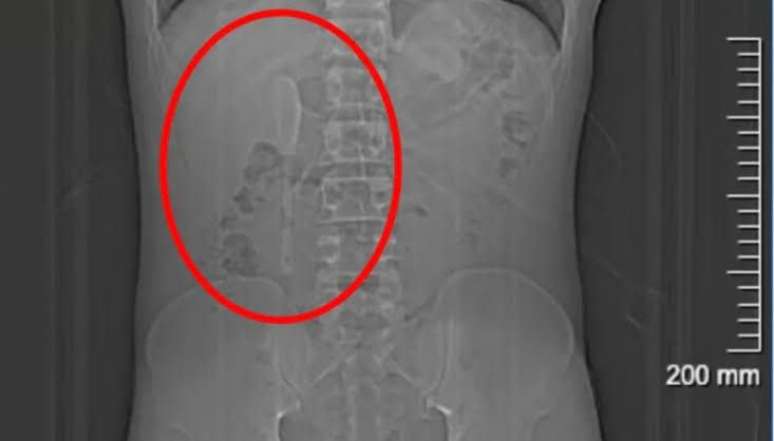

Yan continuou sua rotina normalmente e até praticou exercícios físicos sem apresentar sintomas graves durante os meses seguintes, mas em em junho, procurou um hospital em Xangai, onde exames revelaram a colher presa em uma posição delicada no duodeno.

A cirurgia endoscópica para retirar a colher durou cerca de nove horas e envolveu o uso combinado de dois tipos de pinças para puxar o utensílio de volta ao estômago e, em seguida, removê-la.

Os médicos explicaram que a extração seria difícil devido à superfície lisa da colher e à localização que colocava o intestino em risco de perfuração, podendo causar inflamação ou hemorragia intensa. Apesar do risco, a operação foi bem-sucedida.